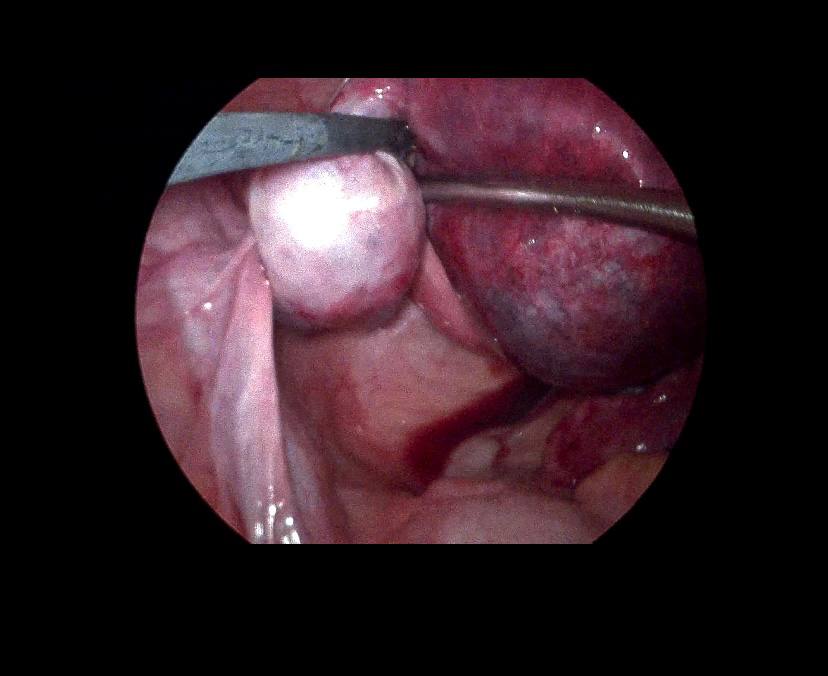

Left ovarian avascular cystic mass 71x68mm , with adjacent left adnexal mass 30x30mm , picture mostly of twisted ovarian pedicle , associated with free fluid >40ml , please for further study to excluded other pathology

Lt ovary is enlarged and edematous, contains 7cm thin wall unilocular cyst “ORADS 1”, there is twisting of its vascular pedicle, picture of ovarian torsion.

operation